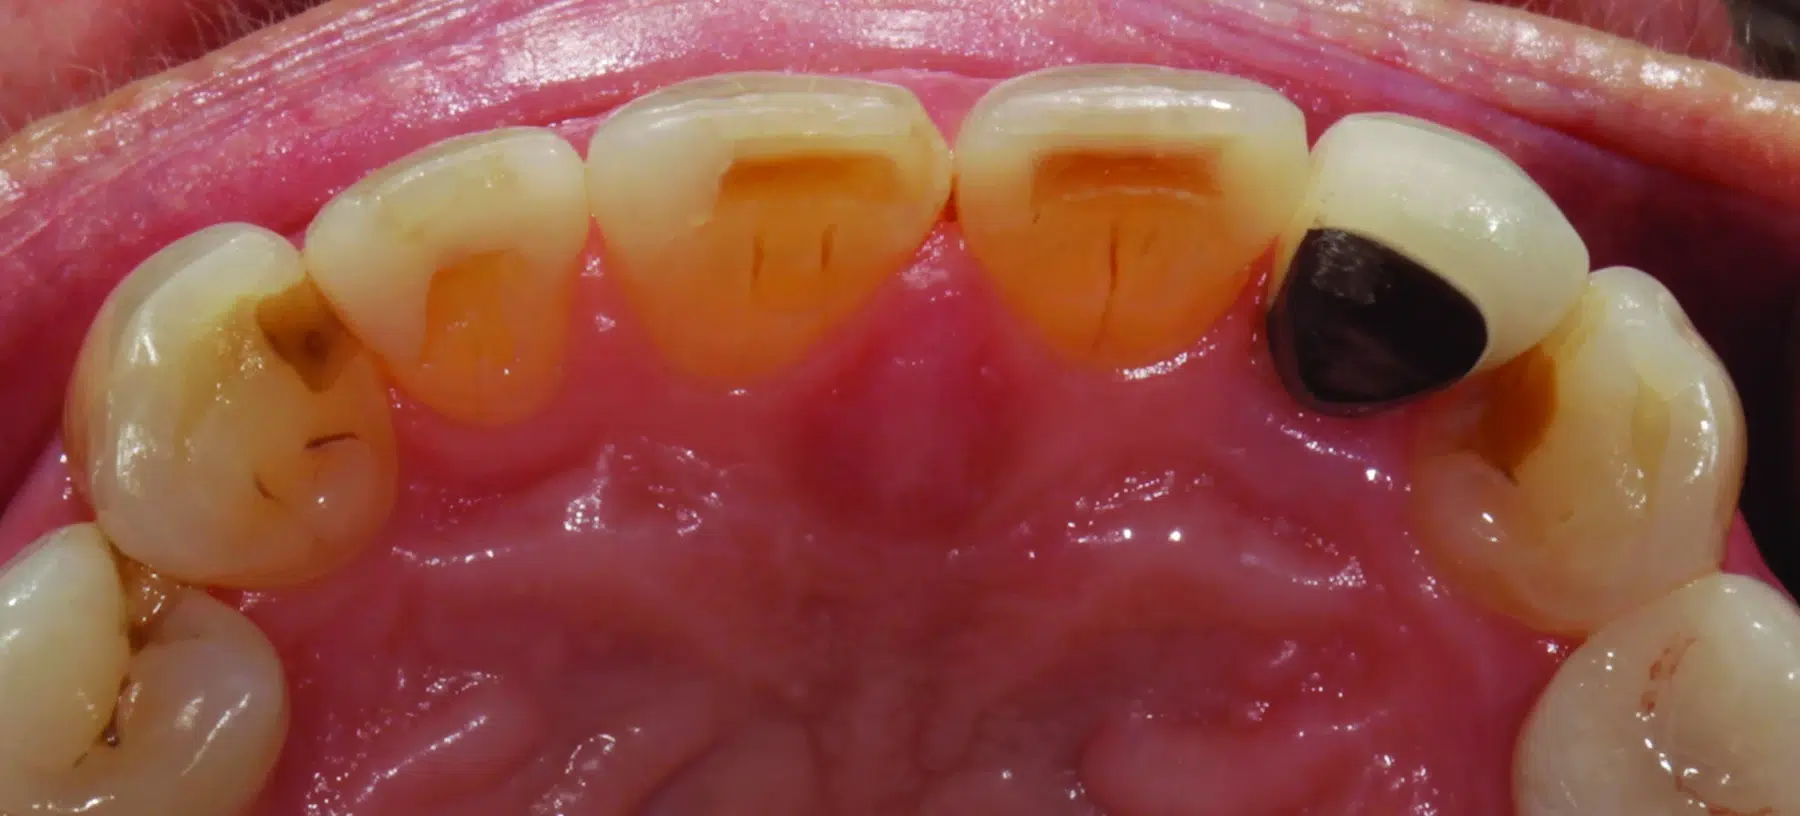

En, sedan många år tillbaka, kvinnlig patient, nu i tidig 70-års ålder kom till praktiken, missnöjd med oestetisk färg och form på tand nr 22 (bild 1). Många år tidigare hade tanden blivit endodontiskt behandlad. En metallpelare hade cementerats för att bygga upp och stärka tanden inför en metallkeramisk krona (bild 2), som utformades så att den skulle maskera stiftets färg. Vid undersökningen påtalade tandläkaren att den mesiala ytan på tand 11 hade flisats av. Han föreslog att den tanden också skulle behandlas, tillsammans med missfärgningarna på tänderna 12 och 21 (bild 3). Den rekommenderade behandlingsplanen innebar att förse tänderna 11-13 och 21-23 med helkeramiska restaurationer. Efter att patienten hade gått med på behandlingsförslaget och innan behandlingen satte i gång, tog tandläkaren en serie extra- och intraorala bilder för kommunikationen med det tandtekniska laboratoriet. Vid behandlingstillfället bedövades patienten och kronan på 22 togs bort och tänderna 11-13 och 21- 23 preparerades för helanatomiska kronor. För att kommunicera pelarfärgen till laboratoriet, fotograferades preparationerna med ett färgprov (IPS Natural Die Material Shade Guide ND7, Ivoclar) (bild 4) och skannades digitalt (Trios 4, 3Shape). Temporära restaurationer framställdes med en prefabricerad skena som hade tillverkats efter starttillfällets diagnostiska design (PerfecTemp II, DenMat).

- (2.) Utgångsläge palatinal bild på överkäkens anteriora tänder. Tand 22 endodontiskt behandlad och försedd med en metallpelare och metallkeramisk krona.